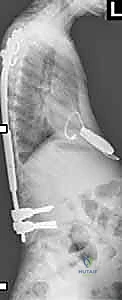

الفكرة العبقرية وراء قضبان النمو هي "التثبيت دون الدمج". يقوم الدكتور هطيف بتثبيت العمود الفقري من الأعلى (عند الفقرات الصدرية العليا) ومن الأسفل (عند الفقرات القطنية أو الحوض) باستخدام مسامير أو خطاطيف تيتانيوم. يتم توصيل هذه المثبتات بقضبان معدنية قوية تمتد عبر منطقة الجنف.

الجزء الأهم: لا يتم دمج (تلحيم) العظام في المنطقة الوسطى المنحنية. هذا يسمح للعمود الفقري بالاستمرار في النمو. مع نمو الطفل، يتم "إطالة" هذه القضبان بشكل دوري لمواكبة زيادة طول الطفل وتصحيح الانحناء تدريجياً.

| قضبان النمو التقليدية (TGR) | يتم إطالتها جراحياً. يحتاج الطفل إلى عملية جراحية صغيرة (تحت تخدير عام) كل 6 أشهر لفتح شق صغير وإطالة القضيب يدوياً. | متوفرة، قوية جداً، أثبتت فعاليتها لعقود. | الحاجة لتكرار العمليات الجراحية والتخدير، خطر العدوى مع كل فتح جراحي. |

- الشق الجراحي: يتم عمل شقين جراحيين منفصلين (أو شق واحد حسب الحالة) في أعلى وأسفل الظهر للوصول إلى نقاط التثبيت، مع الحفاظ على الأنسجة العضلية قدر الإمكان (Minimally Invasive approach).

- تثبيت الدعامات: يتم إدخال مسامير التيتانيوم (Pedicle Screws) أو الخطاطيف بدقة متناهية تحت توجيه الأشعة السينية (Fluoroscopy) في الفقرات العلوية والسفلية.

- إدخال وتشكيل القضبان: يقوم الدكتور هطيف بتشكيل قضبان النمو لتتناسب مع الانحناء الطبيعي المرغوب للظهر، ثم يتم تمريرها تحت العضلات (Submuscular) لتقليل الندبات وتقليل خطر العدوى.

- التصحيح الأولي: يتم ربط القضبان بالمسامير، ويتم إجراء تصحيح أولي آمن للجنف، مع التأكد من إشارات جهاز المراقبة العصبية.

* كيف تتم الإطالة؟ يتم إجراء شق جراحي صغير جداً (حوالي 2-3 سم) فوق منطقة اتصال القضبان. يقوم الدكتور هطيف بفك القفل، وتمديد القضيب بضعة ملليمترات لمواكبة نمو الطفل، ثم إعادة إغلاقه. تستغرق العملية وقتاً قصيراً جداً، وغالباً ما يغادر الطفل المستشفى في نفس اليوم أو اليوم التالي.